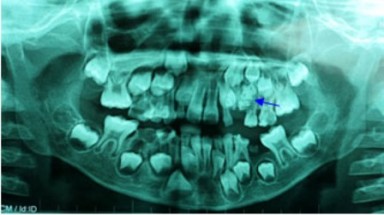

(08:53:02 AM 04/10/2012)(Tin Môi Trường) - Qua chẩn đoán hình ảnh bác sĩ ghi nhận khối gồ này là một "túi răng" nằm chắn ngang đường mọc lên của răng nanh và hai chiếc răng khác.

Từ khóa liên quan: Bé trai, 7 tuổi, mọc, 76, chiếc răng -